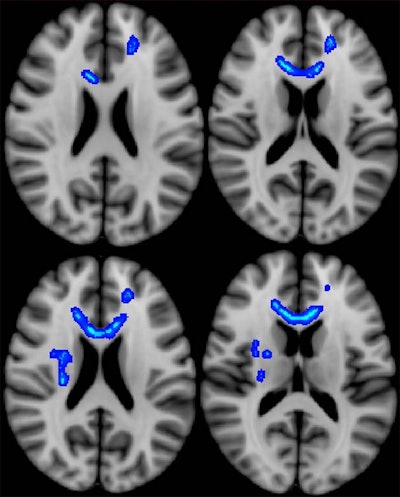

Diffusion-tensor MR images show regions of the brain (blue) in which lower fractional anisotropy correlates with more severe neurobehavioral symptoms. Veterans with the most severe symptoms had lower microstructural integrity in these regions. Image courtesy of Radiology.

Diffusion-tensor MR images show regions of the brain (blue) in which lower fractional anisotropy correlates with more severe neurobehavioral symptoms. Veterans with the most severe symptoms had lower microstructural integrity in these regions. Image courtesy of Radiology.Following initial postdeployment evaluation, 34 study participants (60%) returned to work. Veterans who did not return to work displayed significantly lower fractional anisotropy and higher diffusivity, which suggest less structural integrity, in the left internal capsule, which is associated with motor stimulation to the typically dominant right side of the body.

Thus, the results may provide a connection between impairments in fine motor functioning and the injured veterans' inability to return to work.